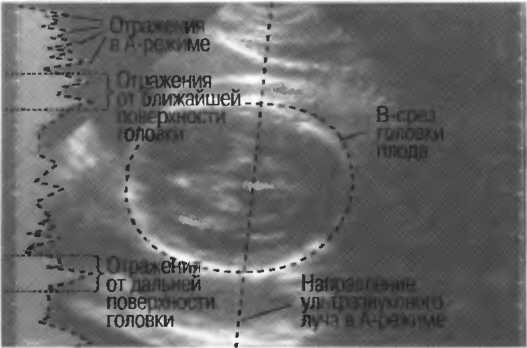

2. В-режим. В этом режиме все ткани, через которые проходит ультразвуковой луч, получают отображение на экране. Получаемые двухмерные изображения называются изображениями в В-режиме или срезами в В-режиме (рис. 16). При быстром чередовании В-срезом получается видеомониторное наблюдение.

1. А-режим. При работе в А-режиме отраженные сигналы изображаются в виде пиков, при этом можно измерить расстояние между двумя различными структурами (рис. 1а). Сама структура в этом режиме не изображается, однако подобный принцип используется и при получении двухмерного изображения.

Рис. 1а. Срез в А-режиме: расположение пиков показывает глубину расположения отражающей структуры. Высота пика определяет интенсивность отраженного сигнала.